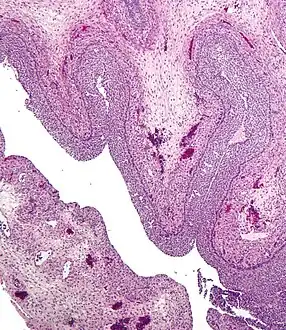

Development and structure

The corpus luteum develops from an ovarian follicle during the luteal phase of the menstrual cycle or oestrous cycle, following the release of a secondary oocyte from the follicle during ovulation. The follicle first forms a corpus hemorrhagicum before it becomes a corpus luteum, but the term refers to the visible collection of blood, left after rupture of the follicle, that secretes progesterone. While the oocyte (later the zygote if fertilization occurs) traverses the fallopian tube into the uterus, the corpus luteum remains in the ovary.

The corpus luteum is typically very large relative to the size of the ovary; in humans, the size of the structure ranges from under 2 cm to 5 cm in diameter.[4]

Its cells develop from the follicular cells surrounding the ovarian follicle.[5] The follicular theca cells luteinize into small luteal cells (thecal-lutein cells) and follicular granulosa cells luteinize into large luteal cells (granulosal-lutein cells) forming the corpus luteum. Progesterone is synthesized from cholesterol by both the large and small luteal cells upon luteal maturation. Cholesterol-LDL complexes bind to receptors on the plasma membrane of luteal cells and are internalized. Cholesterol is released and stored within the cell as cholesterol ester. LDL is recycled for further cholesterol transport. Large luteal cells produce more progesterone due to uninhibited/basal levels of protein kinase A (PKA) activity within the cell. Small luteal cells have LH receptors that regulate PKA activity within the cell. PKA actively phosphorylates steroidogenic acute regulatory protein (StAR) and translocator protein to transport cholesterol from the outer mitochondrial membrane to the inner mitochondrial membrane.[6]